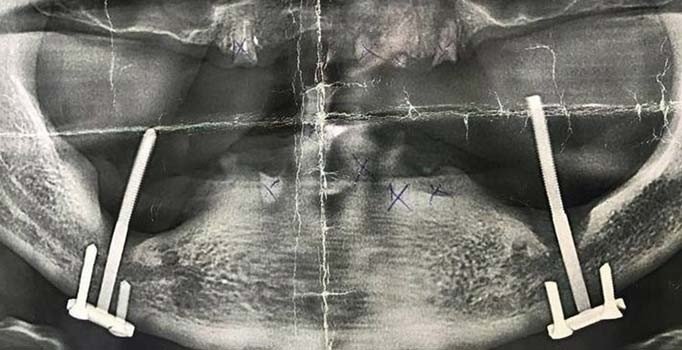

İnşaat çivisiyle implant! 28 yıl sonra fark edildi Güncel 15 Nisan 2019, 18:09 yayınlandı 15 Nisan 2019, 20:07 güncellendi